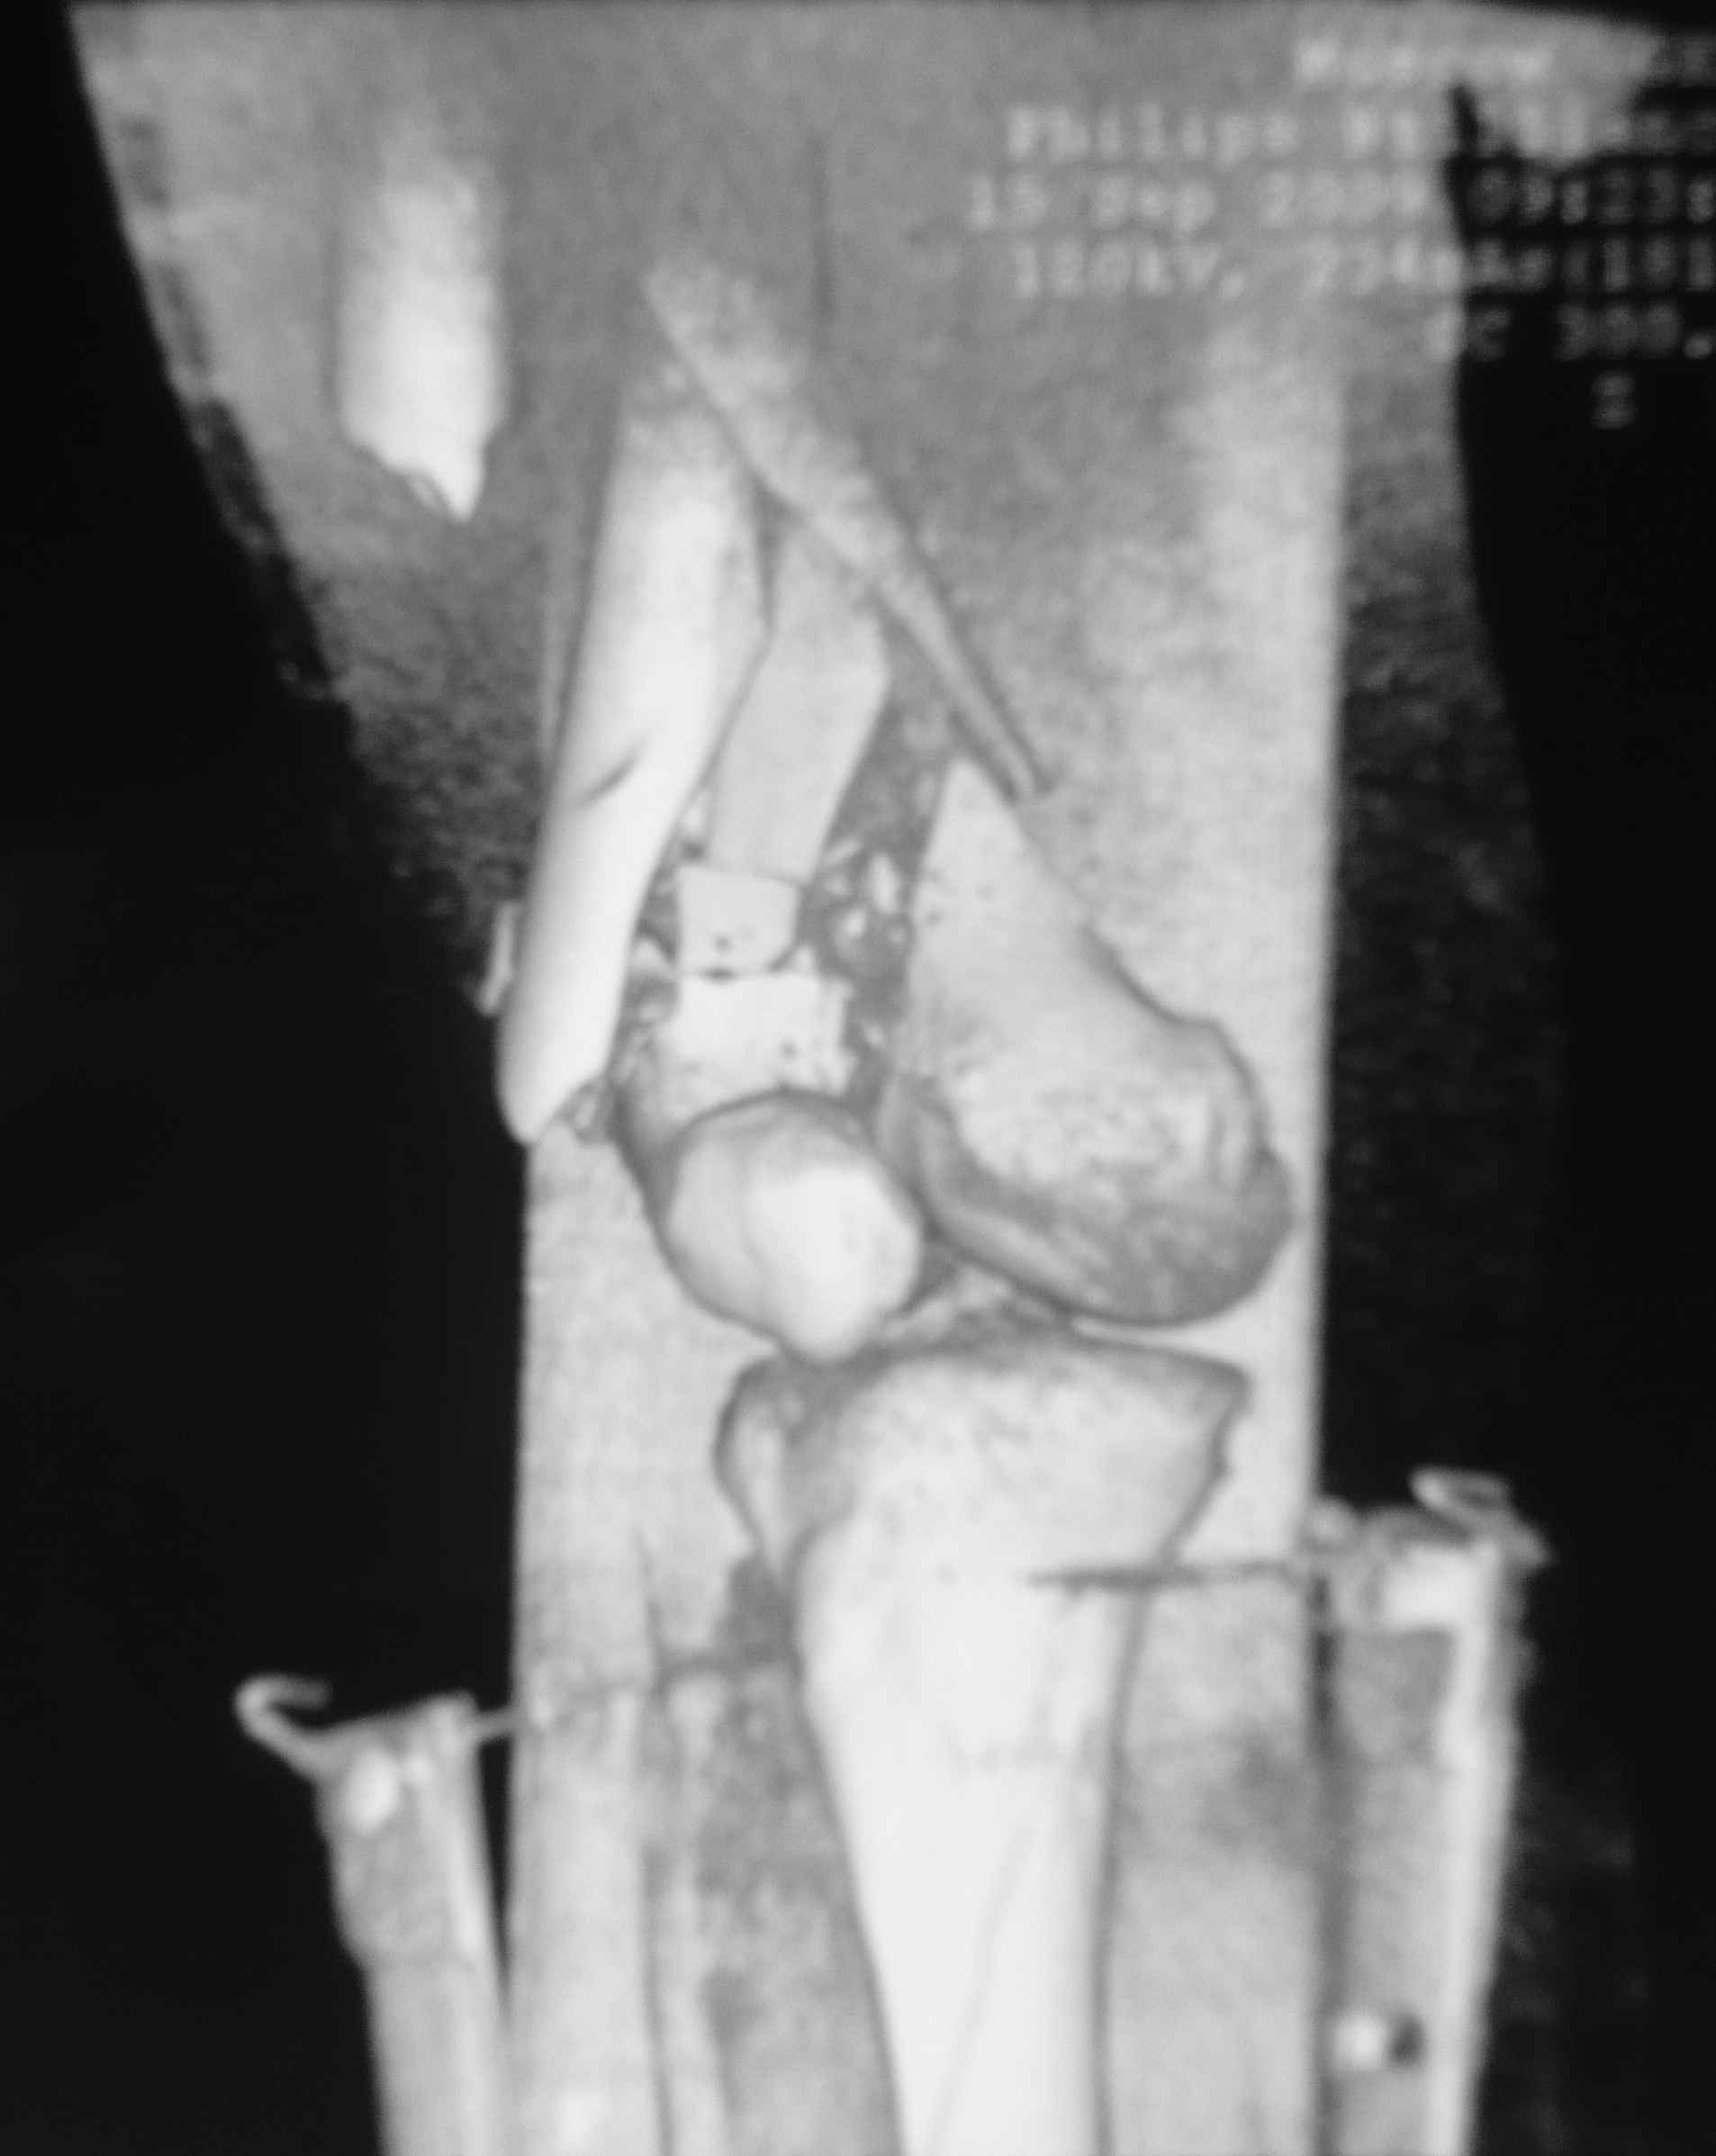

еще кт

я совсем молодой доктор так что без обид могу ошибаться во многом.

Это перелом не нижней трети, а дистального суставного конца, с распространением на диафиз. Что-то между C2 и C3. Но пока ближе к C2 по увиденному - вторую проекцию еще не показали.

На профиле стало видно, что открываться придется, это перелом C3, хотя можно назвать и C2+, т.е. с еще и фронтальным раскалыванием одного мыщелка. Надо сделать медиальную артротомию, ступеньку на внутреннем мыщелке устранить, ввести либо несколько временных спиц спереди назад, или сразу винт вдоль эллипса мыщелка. А дальше как выше написано - дистрактор, и штифтовать. Учитывая наличие открытого колена - вполне уместно ретроградно.